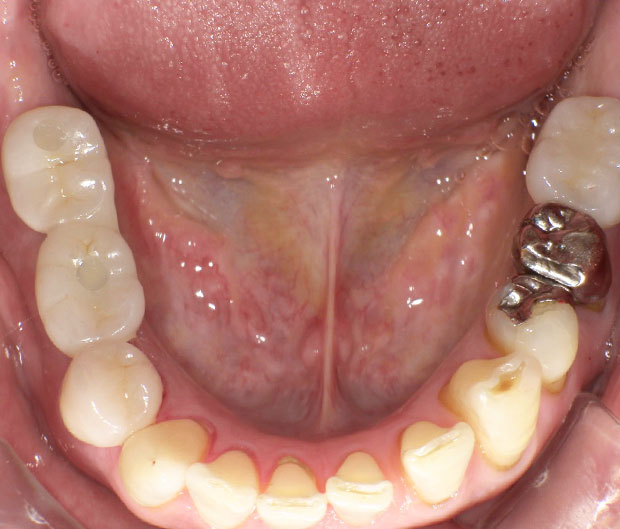

上物が入った状態です。

非常に綺麗にセットすることができました。

(4番目も銀歯で気になるとのことなので被せ直しました)